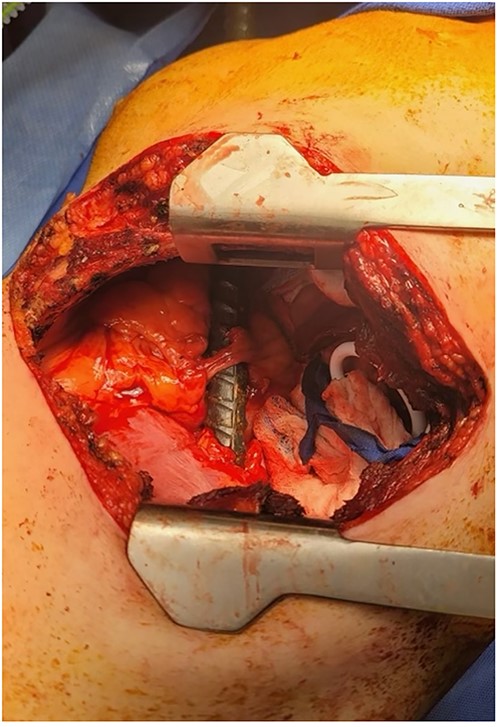

Once in the operating room, the patient was placed in a semi-lateral, right-sided decubitus position exposing the left side of the chest. A left thoracotomy was performed in the sixth intercostal space and the pleural cavity was entered. At this time, we were able to visualize the rebar in the posteromedial left chest with a clear site of penetration through the diaphragm close to the pericardium and through the left anterior chest, and we were making contact with the phrenic nerve (Fig. 3). Intraoperative transesophageal echocardiogram confirmed no intrapericardial injury, and direct visualization revealed no pleural fluid. Afterward, a left subcostal incision was made in the abdomen, which demonstrated a posterolateral splenic injury. Digital control of the splenic hilum and thoracic bleeding were controlled and the rebar was removed through the right flank. Once removed, improved visualization revealed two separate diaphragmatic full-thickness lacerations, which were primarily repaired. Two chest tubes were placed and the thoracotomy incision was closed.

Thoracotomy incision revealing the rebar penetrating the diaphragm and coming in contact with the phrenic nerve.